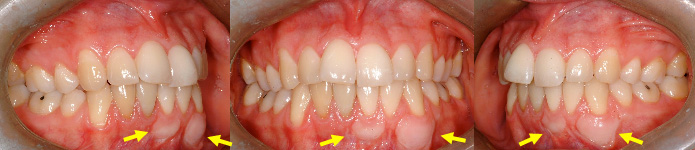

(A, C) Une incisive inférieure avancée présente un niveau de gencive plus bas avant le traitement (flèche bleue). Une autre incisive plus reculée a un niveau de gencive plus haut (flèche jaune). (B et D) Les corrections orthodontiques ont égalisé les dents. Le niveau de gencive ne s’est pas détérioré sur l’incisive avancée (bleu) qui fut légèrement reculée pendant le traitement tandis que le niveau de l’autre incisive (jaune) a diminué lorsqu’elle fut avancée. Ceci a en fait régularisé le niveau de gencive de ces dents et tant qu’il demeure stable, aucune intervention n’est nécessaire. L’hygiène buccale contribuera à la santé de la gencive et au maintien de sa hauteur (à noter la présence d’inflammation sur le bord des incisives à la fin du traitement (B, D). (Femme de 25 ans)